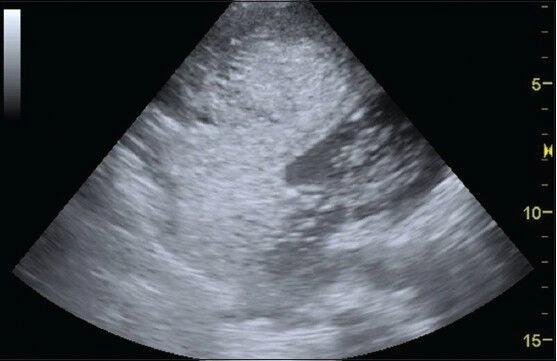

There is increasing interest in the use of ultrasound to assess and guide the management of critically ill patients. The ability to carry out quick examinations by the bedside to answer specific clinical queries as well as repeatability are clear advantages in an acute care setting. In addition, delays associated with transfer of patients out of the Intensive Care Unit (ICU) and exposure to ionizing radiation may also be avoided. Ultrasonographic imaging looks set to evolve and complement clinical examination of acutely ill patients, offering quick answers by the bedside. In this two-part narrative review, we describe the applications of ultrasonography with a special focus on the management of the critically ill. Part I explores the utility of echocardiography in the ICU, with emphasis on its usefulness in the management of hemodynamically unstable patients. We also discuss lung ultrasonography - a vastly underutilized technology for several years, until intensivists began to realize its usefulness, and obvious advantages over chest radiography. Ultrasonography is rapidly emerging as an important tool in the hands of intensive care physicians.

超声在评估和指导危重症患者管理方面的应用正受到越来越多的关注。在床边进行快速检查以回答特定临床问题的能力以及可重复性,在急性护理环境中具有明显优势。此外,还可避免与将患者转出重症监护病房(ICU)相关的延误以及暴露于电离辐射。超声成像似乎将不断发展并补充对急重症患者的临床检查,在床边提供快速答案。在这篇分两部分的叙述性综述中,我们描述超声检查的应用,特别关注危重症的管理。第一部分探讨超声心动图在ICU中的效用,重点是其在血流动力学不稳定患者管理中的作用。我们还讨论肺部超声检查——这项技术多年来未得到充分利用,直到重症医学专家开始认识到其效用以及相对于胸部X线摄影的明显优势。超声检查正迅速成为重症监护医师手中的一项重要工具。